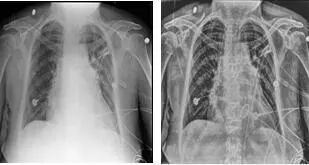

3.体检专用套件:DRX-Compass X针对这一特殊领域配置了尘肺病检查模式,从摄影条件、图像处理方式按照相关国家标准设置,从而可以提供符合规范的标准数字化X射线影像;系统配置了Bone suppression software 骨抑制成像软件,可通过软件后处理去除胸部前后位及后前位的后肋及锁骨显示,帮助医生更清楚的在体检阅片过程中识别肺部软组织病变如肺结节、气胸等。